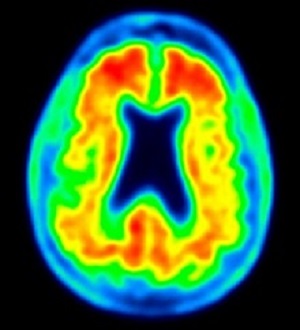

AlzheimersA simple new charting tool that tracks cognitive performance in adults aims to help physicians identify people who may be on the path to Alzheimer disease or another form of dementia. The tool is called the QuoCo (cognitive quotient).

Dementia is a growing problem world-wide with many undiagnosed cases. Although there are no cures, potential treatments are being tested and some risk factors, such as diet and exercise, can be addressed to delay onset.

"Dementing illnesses have reached pandemic levels," write the authors. "Early detection of cognitive impairment remains our best approach to disease management before irreversible brain damage occurs. Family physicians are in a key position to contribute to this approach; however, they are ill-equipped."